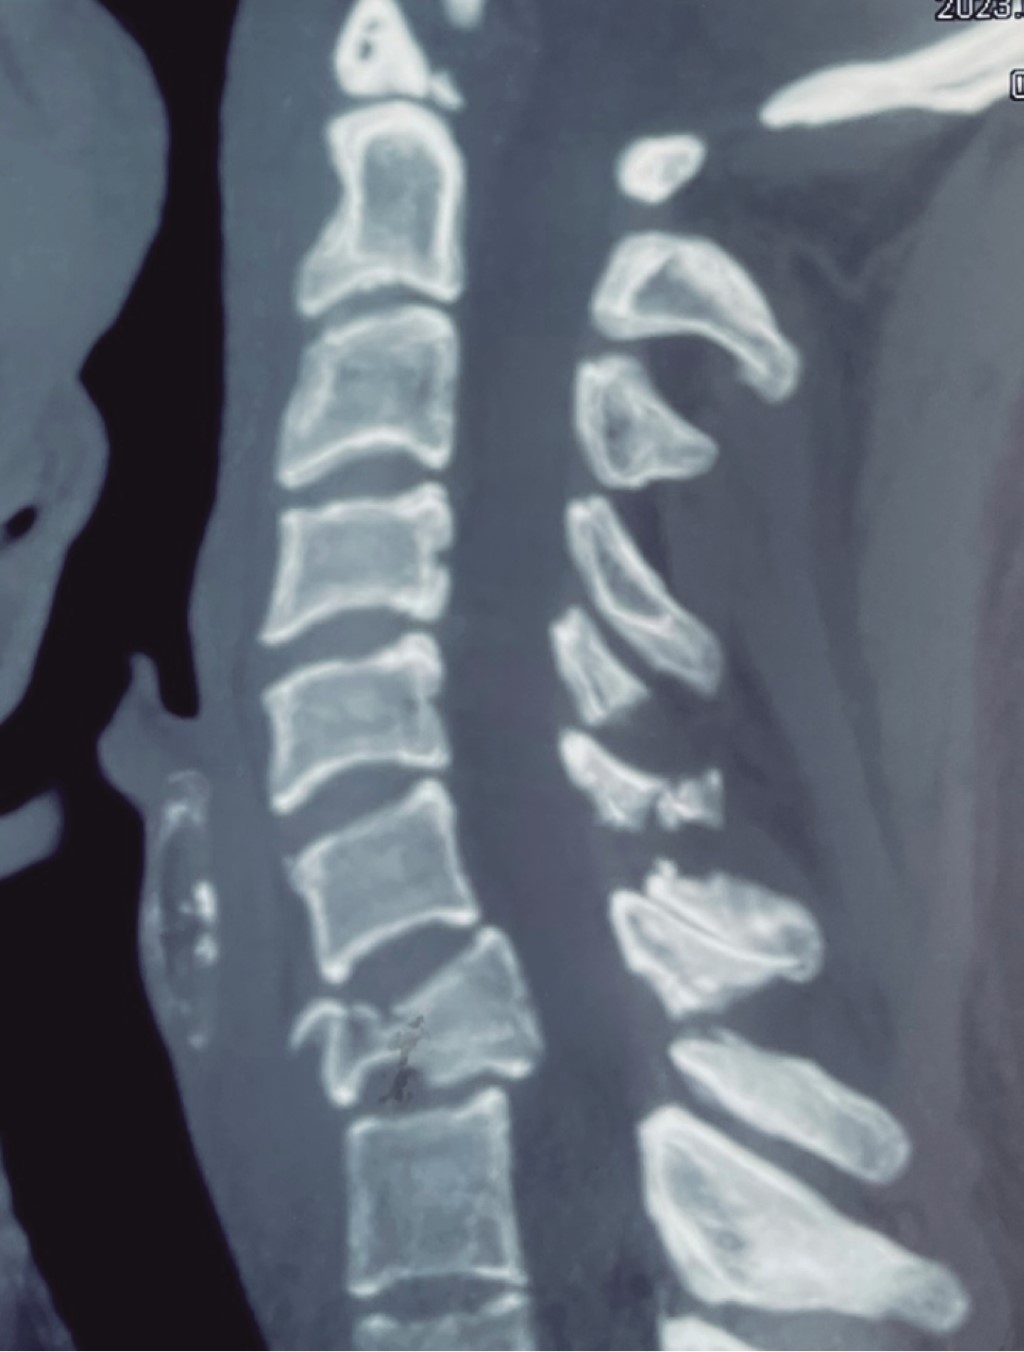

Se presenta el caso de un paciente masculino de 33 años de edad, sin comorbilidades, que acude al servicio de urgencias por presentar cervicalgia de dos semanas de evolución posterior a un accidente en motocicleta. Las radiografías iniciales tomadas en el hospital de primera atención no fueron valorables para diagnóstico; se toman radiografías y tomografía axial computarizada (TAC) de columna cervical (Figuras 1, 2 y 3), diagnosticando fractura de C1 y C7 donde se observa fractura por compresión de C7 AO B2 y C1 con fractura de arco anterior y posterior izquierdo con desplazamiento coronal > 7 mm de la masa lateral izquierda. En la resonancia magnética T2 axial, se observa lesión del ligamento transverso. En resonancia magnética simple se observa fractura de cuerpo vertebral de C7, con compromiso de conducto raquídeo